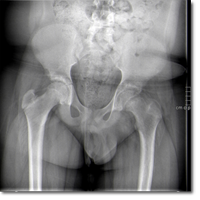

Niña de 10 años de edad con incapacidad para extender completamente la articulación...

Barrenechea García I, Álvarez Zallo N, Sánchez-Guardamino Sáenz D.

28 octubre 2025

Valoración